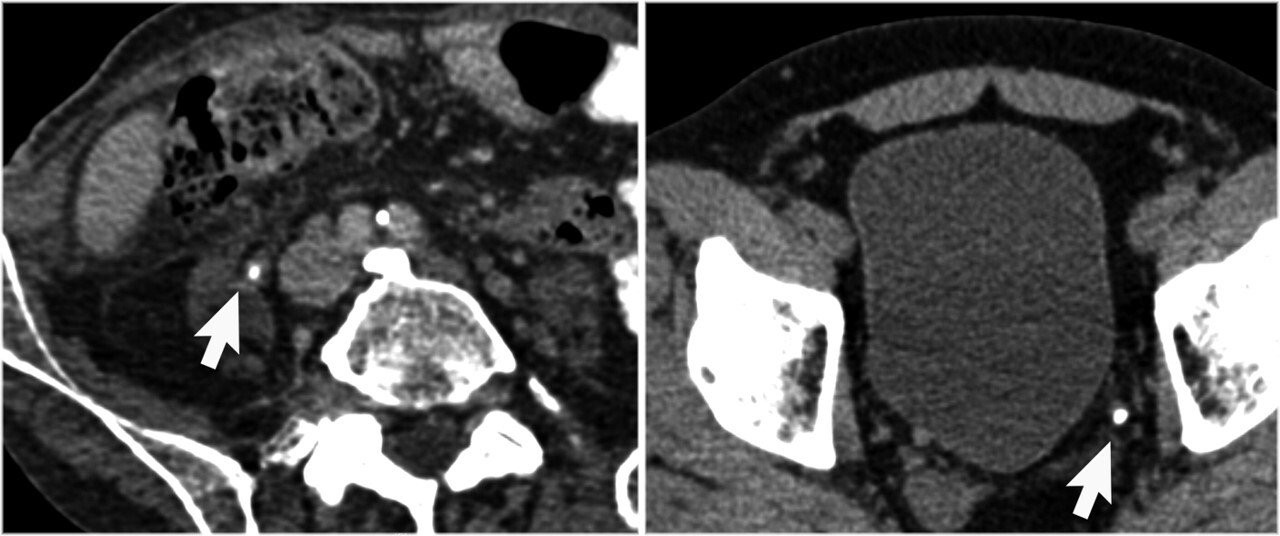

9

Q

What pathology is seen here?

A

Ectopic Kidney

10